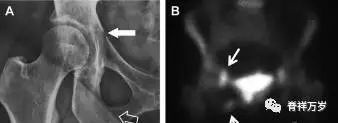

股骨头骨折

股骨头骨折常与髋关节脱位有关。需要关注的是那些既不是因剪力损伤也不是因直接*力暴**作用造成的骨折。这些类型的骨折可能十分轻微。提倡应用 CT 检查,不仅可诊断骨折,而且能评估关节内骨折碎片的位置(图 5)。

图 5 股骨颈骨折伴髋关节脱位。A 股骨头上外侧轮廓缺失(空箭头)关注嵌入上方关节间隙的骨折碎片(黑色箭头)B 冠状位 CT 多维重建(MPR)证实骨软骨碎片(白色箭头)和关节上方的另一个碎片(空箭头)